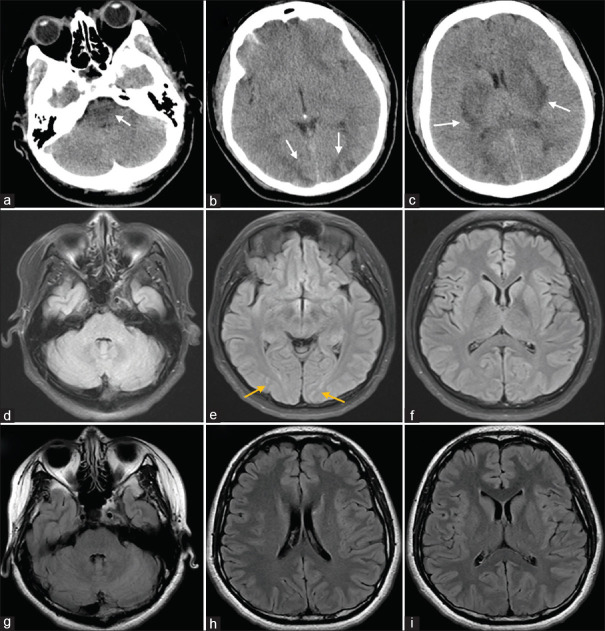

Posterior reversible encephalopathy syndrome (PRES) is a rare neurological disorder with no specific clinical symptoms in the early stage; thus, early imaging identification is of great importance. A 29-year-old pregnant woman at 37 weeks experienced sudden generalized seizures accompanied by impaired consciousness. Brain computed tomography, conducted around 3 h after the onset, revealed symmetric areas of decreased density in the basal ganglia, brainstem, and suboccipital cortex, along with cerebral swelling. Following treatment with positive inotrope, diuretics, antihypertensives, and dehydration therapy, the patient regained clear consciousness on the 2nd day. On the 9th day postonset, a follow-up contrast-enhanced magnetic resonance imaging (MRI) showed slightly elevated signals in the bilateral occipital lobes on the T2 fluid-attenuated inversion recovery sequence. A subsequent brain MRI on day 47 postonset indicated no significant abnormal changes. Neuroimaging is pivotal for PRES diagnosis, revealing typical signs of widespread vasogenic edema in the posterior brain white matter, affecting the occipital lobes, cerebellum, brainstem, thalamus, and basal ganglia. With timely treatment, these lesions can partially or completely resolve within days or weeks.